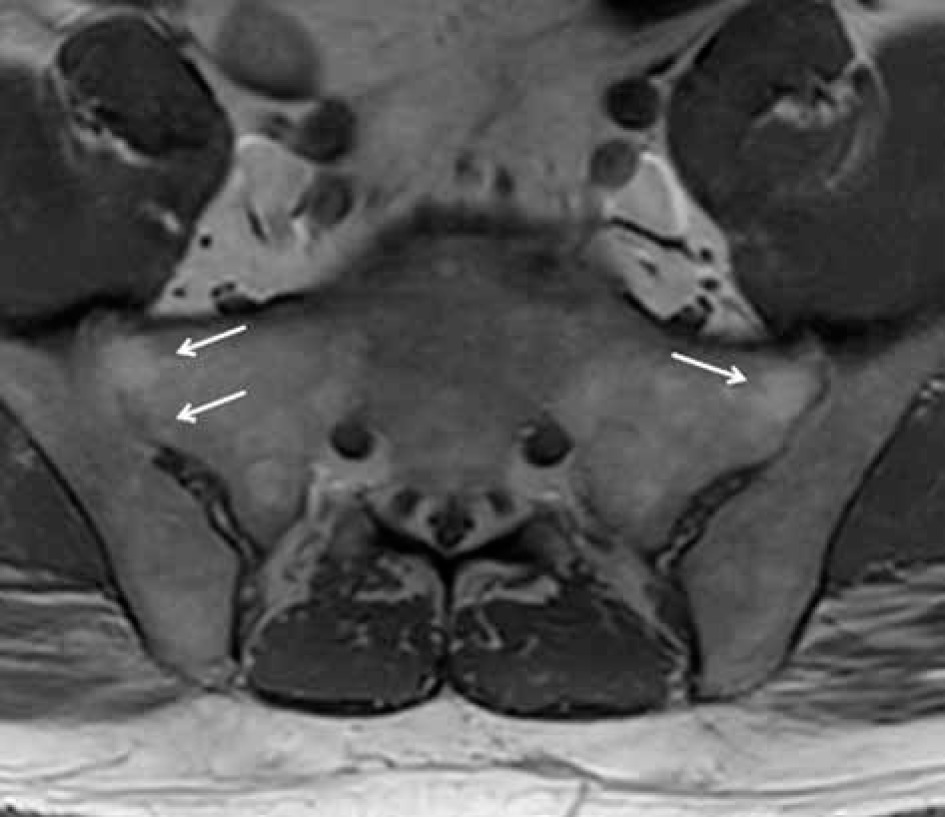

Figure 17

A 57-year-old male with longstanding ankylosing spondylitis (AS). Axial T1-weighted (T1W) magnetic resonance (MR) image shows osseous fusion of the right greater than left sacroiliac joints (arrows) with areas of high signal intensity prominent fatty marrow on the sacral sides in keeping with post-inflammatory change